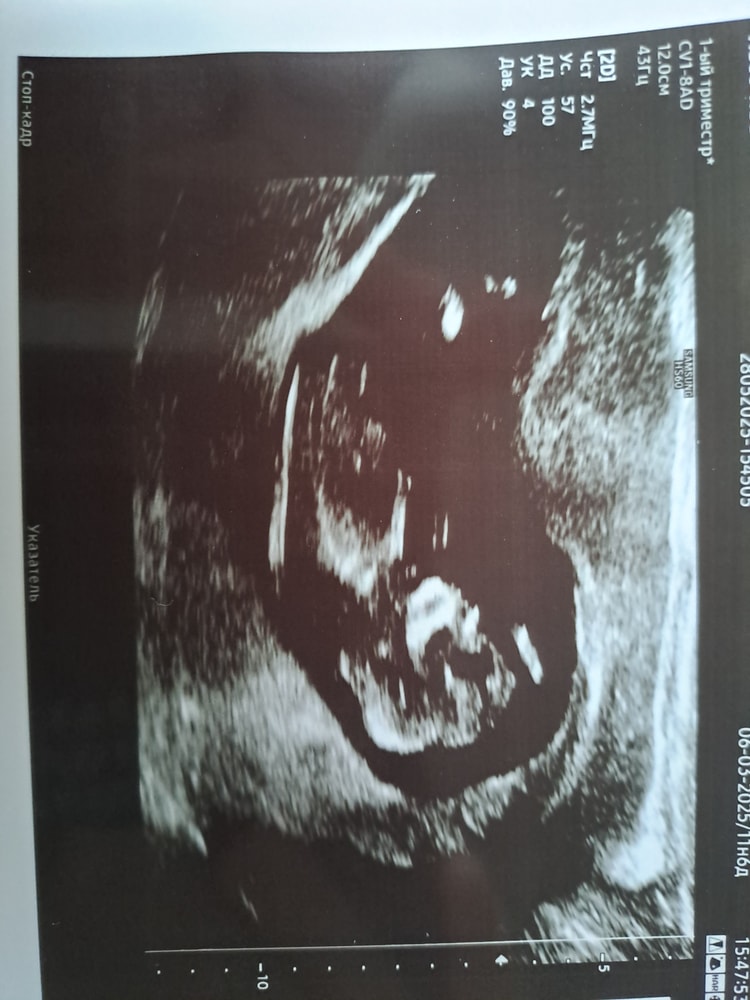

Анализы, скринингиВот и пролетело время моментально. И уже первый скрининг сегодня прошёл. Врач сказала, что по узи все отлично. Кроха активничала во всю, трогала свое лицо ручками, это было так здорово смотреть😍 но я буду не я, если не спрошу несколько вопросов. Твп 2.3, где-то нашла, что норма до 3, в другом месте до 2.2, в итоге мы в норме или нет? PI в маточных артериях слева 1.60, справа 2,23, норма ли? Ну и видно ли тут половой бугорок? Врач посмотрела пол, но снизу, как на более поздних сроках. Она сказала предположение, но предупредила, что лучше в 16 недель посмотреть. И совсем забыла там спросить, кровь же придёт в жк? Или надо ехать за результатом?

Именно по этому фото ничего не видно.Не понимаю в чем сложность для опытных узистов 🤯У меня пятая Б и ни разу не ошиблись с 12 недель

Да, ТВП 2.3 это нормально, до 3 мм считается в пределах нормы. По PI чуть высоковато, но врач скажет, что с этим делать, могут просто наблюдать. Пол ещё рано точно говорить, лучше подождать до 16 недель. Кровь обычно приходит в ЖК, но можно уточнить у медсестры или на приёме.

На маточные артерии на этом сроке можно не обращать внимания) у меня тоже разные были. Твп норма